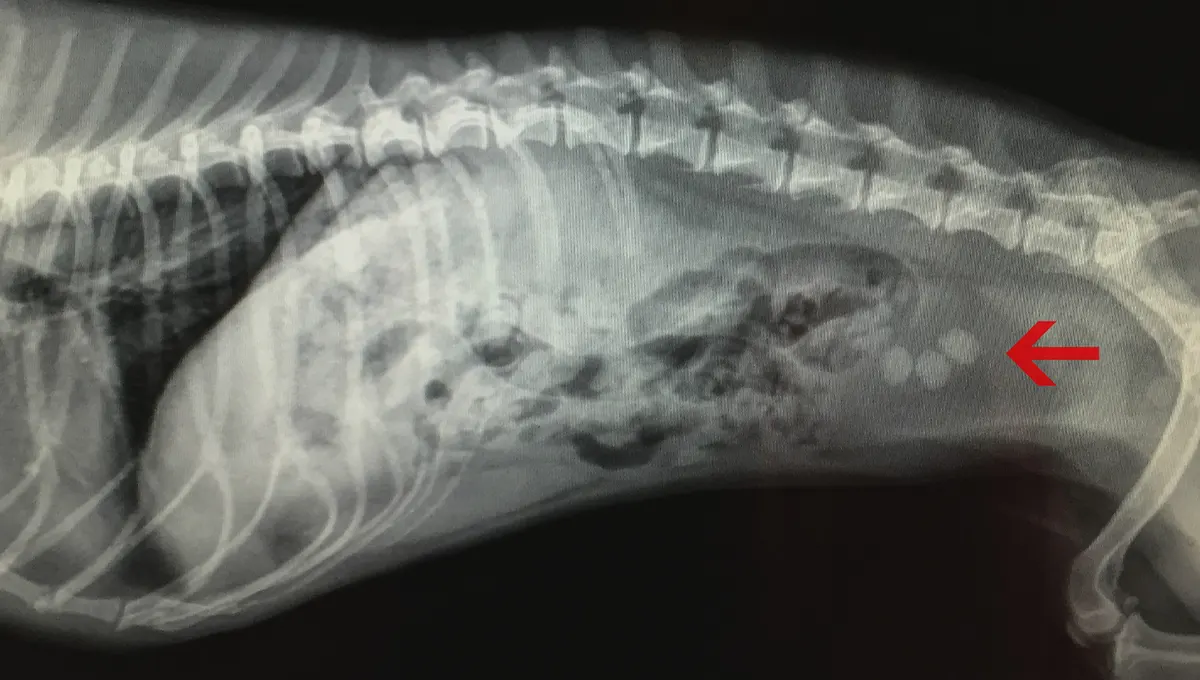

Симптомы болезни почек у собак